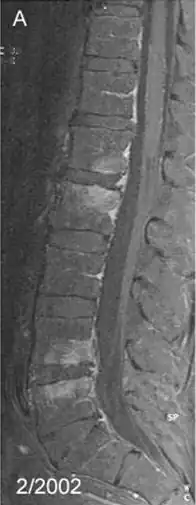

Spondylodiscite due à Tropheryma whipplei. IRM en T1 montrant des lésions (plus claires) de spondylodiscite sur les vertèbres L1, L2, L4 et L5, touchant également les disques intervertébraux.

L'IRM

Effectué lorsque la scintigraphie osseuse montre un foyer de fixation, mais que les radiologies standards sont normales (souvent en début de maladie). On recherches les mêmes signes qu'en radiologie standard.